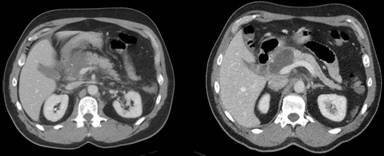

We present a 61-year-old patient who presented to an outside hospital with sudden onset of acute abdominal pain, nausea, and vomiting lasting for two days. Subsequently the patient was admitted with a diagnosis of acute pancreatitis of unknown etiology. At the time of admission laboratory evaluation revealed serum lipase to be significantly elevated at 5,367 units/L. CT scan of the abdomen was consistent with the diagnosis of acute pancreatitis as shown in Figure 1.

Figure 1. CT scan of the abdomen was consistent with the diagnosis of acute pancreatitis. |